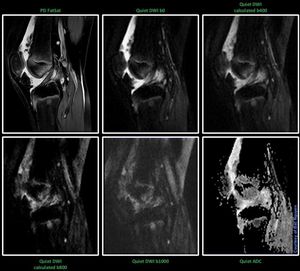

MR MSK Imaging – Quiet DWI @ Siemens 1.5T Aera It’s cool to see the potential with Quiet DWI outside the brain. This is not the best example, but great possibilities are out there for further optimizing. Interesting.#s_mri #siemens #mri #quiet_suite